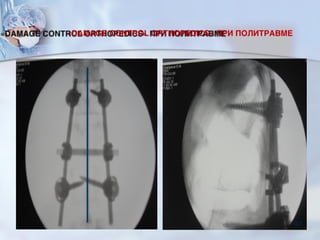

«DAMAGE CONTROL ORTHOPEDICS» ПРИ ПОЛИТРАВМЕ

Современная концепция лечения критических состояний при политравме

■ Damage control- в 1990 гг, предложена Гановерской школой (H.

Pape et all.2002) философия которой заключается в том, что

оперативное лечение как внутренних органов, так и ОДА

разделяются на 2 этапа:

■ Первым этапом проводят операции по жизненным показаниям, а

переломы костей фиксируют стержневыми АВФ.

■ Вторым этапом – малоинвазиный остеосинтез переломов длинных

костей (ЧКДО, БИОС, LISS).

Закрытый малоинвазивный остеосинтез (CILO, LISS,

ExFix) – метод выбора для пострадавших с

политравмой во втором «клиническом этапе» лечения.

■Не сопровождается кровопотерей;

■Высокая прочность фиксации;

■Малый риск инфекционных

осложнений;

■Возможность ранней функции. 93